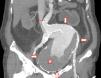

Abdomen agudo de presentación atípica

Acute abdominal pain with atypical presentation